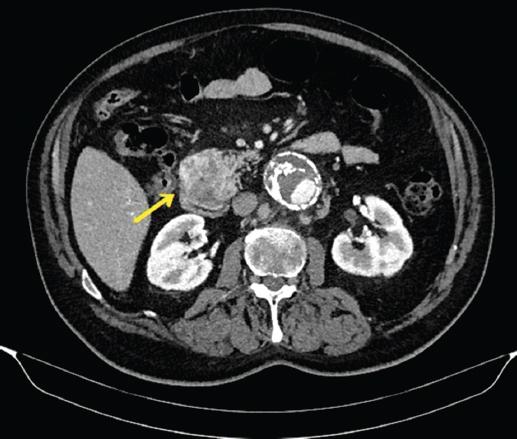

A los dos años de la cirugía se diagnostica mediante tomografía computarizada toraco-abdomino-pélvico de una masa heterogénea de 50 x 47 mm en la encrucijada duodenopancreática sin dilatación de la vía biliar ni del conducto de Wirsung (Fig. 1). Una biopsia percutánea orienta a un origen sarcomatoide de la masa, por lo que se decide realizar una duodenopancreatectomía cefálica (Figs. 2 y 3). El diagnóstico anatomopatológico confirma una metástasis de SPI de 5 x 4,5 x 4,2 cm originada en el proceso uncinado pancreático, bordes libres de tumor y adenopatías negativas (Fig. 4). El paciente presentó una buena evolución postoperatoria, sin complicaciones. En el seguimiento al año permanece asintomático y sin signos de recidiva.

Figura 1 Corte axial de tomografía abdominal: masa sólida y heterogénea de 50 x 47 mm en la encrucijada duodenopancreática.